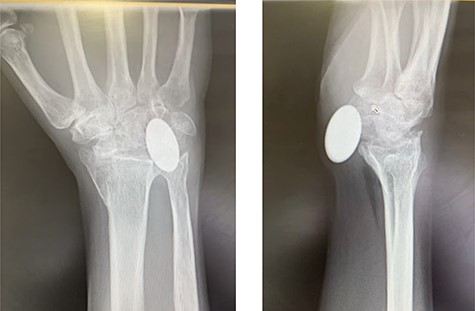

Radiographs demonstrated that the Pyrocarbon implant was palmarly displaced and rotated 90 degrees; it had migrated into the carpal tunnel/ distal forearm (Fig. 2). The clinical diagnosis was compression of the ulnar due to the migration of implant. Surgery was carried out 1 month later during which the Pyrocarbon Amandys wrist implant was removed through a volar approach (Fig. 3) and total wrist fusion was performed using a straight Arbeitsgemeinschaft für Osteosynthesefragen (AO) wrist fusion plate (Fig. 4). The surgery successfully relieved all wrist pain and was accompanied by prompt resolution of symptoms of ulnar nerve compression; she was discharged from follow-up approximately 3 months after surgery.

Intra-operative clinical photographs of the migrated pyrocarbon implant.